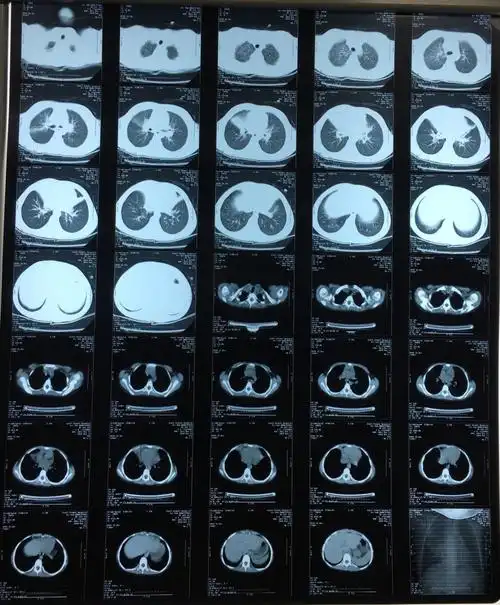

入院后查胸部ct提示右肺中叶及左肺舌叶肺炎

肺部ct提示双下肺肺炎,右侧为著